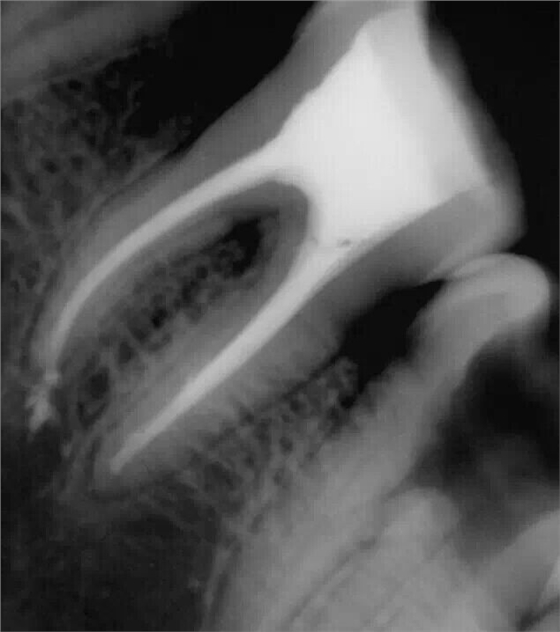

忘記照術(shù)前片了,補一張去腐后的照片。在進(jìn)行根管預(yù)備的時候D7遠(yuǎn)中出現(xiàn)器械分離

震出一半時照的X片